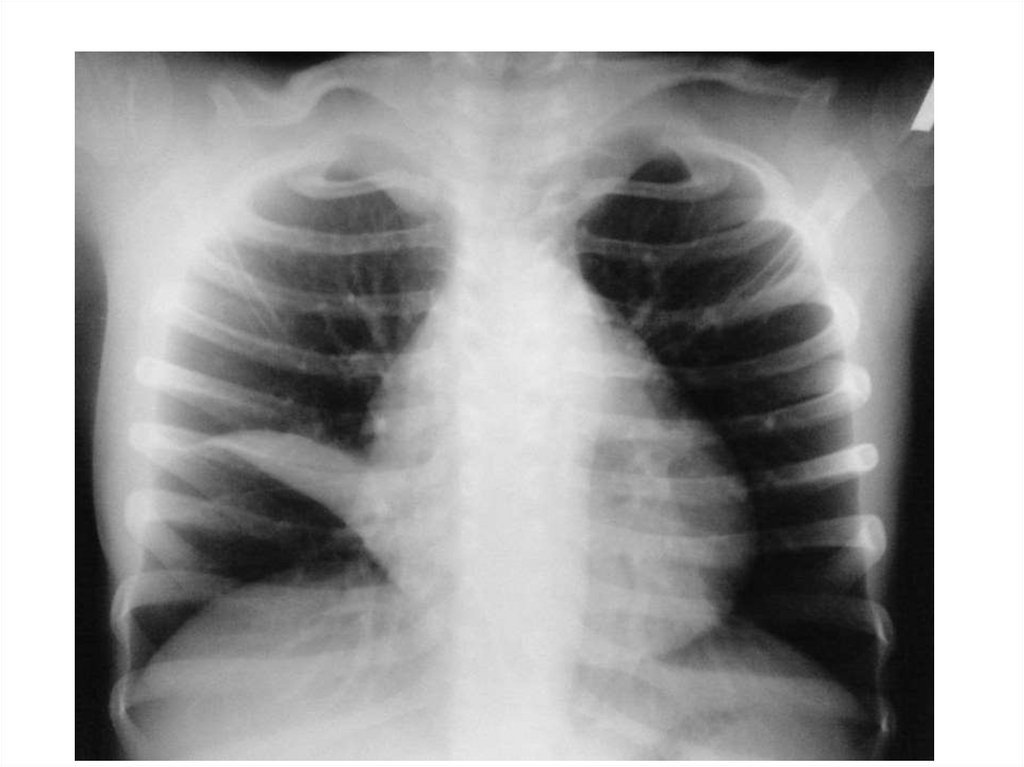

Эмфизема

16.

17.